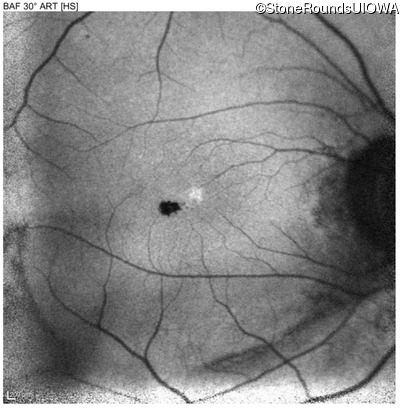

Blue Autofluorescence - Right - 20/25

Exemplar